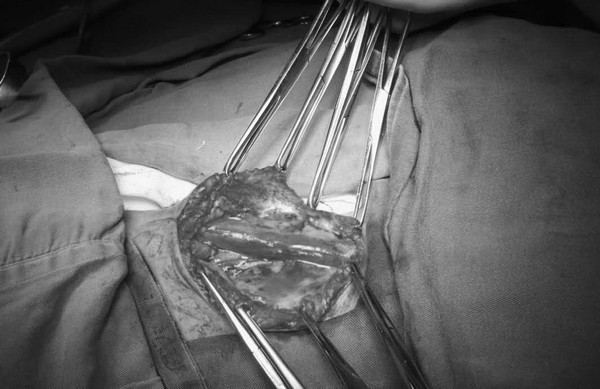

手术切开皮肤可见瘤体巨大

手术如期进行,王兵教授亲自主刀,崔文军副主任作为助手。刚刚切开患者的表皮即看见蓝色的瘤体,因为平卧时瘤体充血,显得特别大,手术必须非常谨慎,瘤体稍有损伤即血流不止,难以控制。王兵教授凭借着熟练的手法、精细的操作,崔文军副主任密切配合,顺利地将瘤体分离,瘤体的的底部有三个部位与颈内静脉连接,如果手术中操作不慎,就有可能导致患者颈内静脉撕裂甚至扯断,后果不堪设想。王兵教授凭借丰富的经验,细心地将这三个部位分离出来并结扎,完整保留了右侧颈内静脉,手术非常顺利,出血量不足100ml。颈部皮肤缝合后进行双下肢静脉曲张治疗,采用大隐静脉剥脱结合激光治疗手段,将患者双下肢曲张血管完美的处理,创伤小,治疗彻底,而且美观。